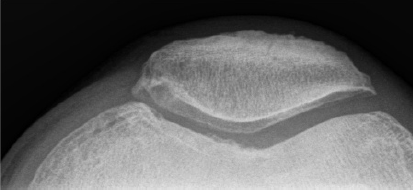

Quels sont les 4 signes radiologiques de l’arthrose?

Classiquement, les trois premiers signes sont retrouvés dans les stades radiographiques légers, modérés et avancés. La présence des kystes sous-chondraux est plus rare.

**Exemple d’ostéophyte : la petite crotte genre sur la rotule à gauche, c’est vrm minuscule, bin c’est ca.